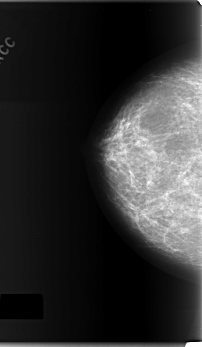

C_0165_1.LEFT_CC

LEFT_CC LINES 5992 PIXELS_PER_LINE 3472 BITS_PER_PIXEL 12 RESOLUTION 50 OVERLAY